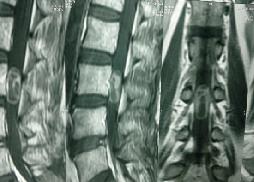

Large Intradural Dermoid